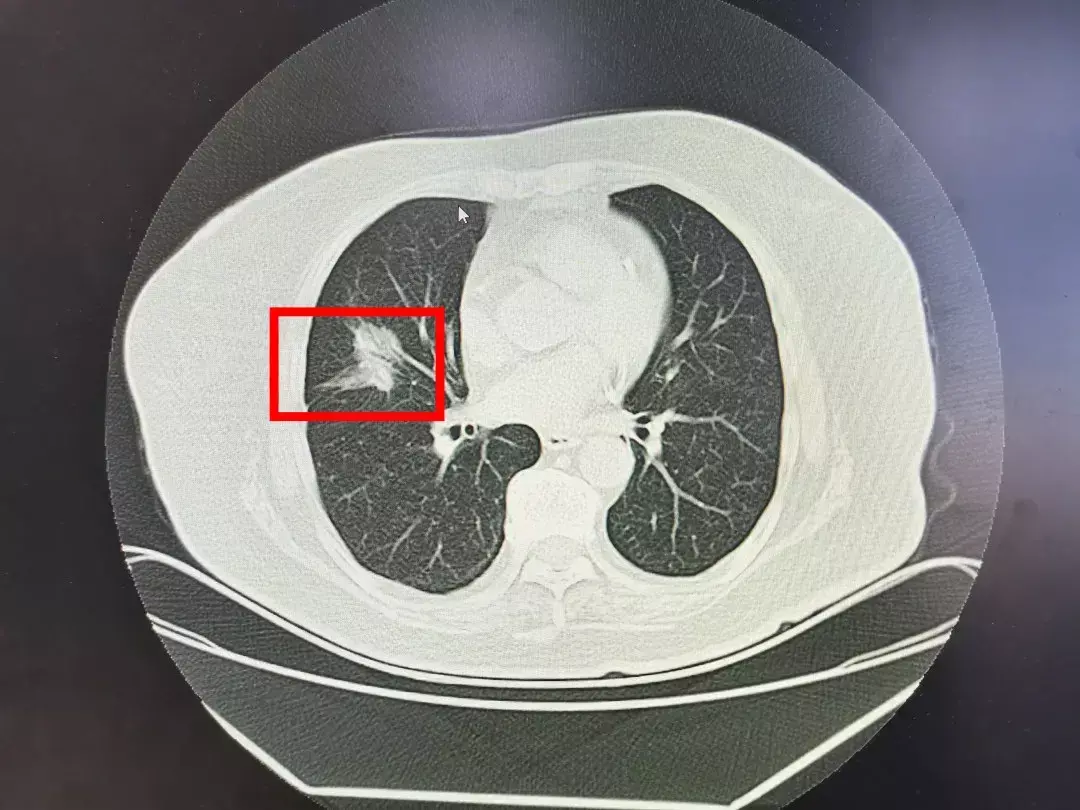

他儿子广先生觉得事情可能没那么简单,带着老太太来到西安市人民医院·西安市第四医院新院区胸部疾病治疗中心杨锋主任的门诊。杨主任详细的询问了老太太的病史,并复查了一下胸部CT胸部CT上这个阴影有3.5*2cmCT,检查结果:红色方框为阴影部分,确实不是打个“消炎针”就能消除的。考虑是肺癌。